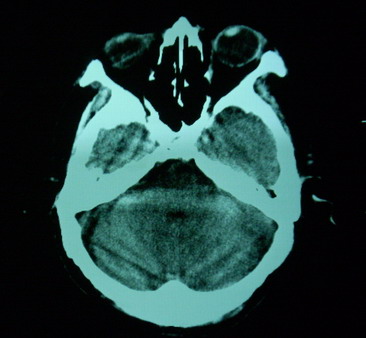

男,70岁,左侧肢体活动障碍口角向右侧歪斜2天,有高bp病史

pe:神情,能与之正常交流,吐字不清,180/90mmhg,双瞳孔无异常,左侧肢体肌力1级 b(+)

图中有个同心圆壮低密度影是ct伪影,见笑了。

1、右侧基底区及外囊区腔隙性脑梗塞。2、脑萎缩。

右基底节内囊前支区腔隙性脑梗塞,脑萎缩

右基底节区脑强隙 右基底节区低密度影密度太低 边界清 不会是2天的梗赛灶

2天左右的腔隙性脑梗死ct多难以发现 何况你的机器又差 很难显示 即使显示密度应该略低影

边缘模糊